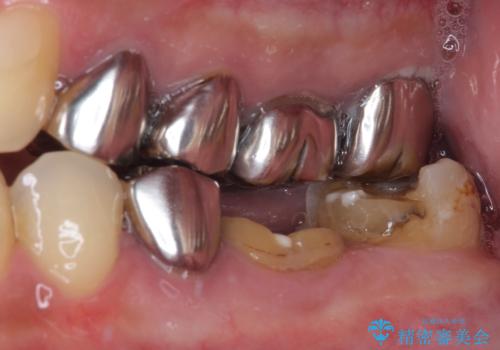

- 下顎左右の奥歯を治療途中で放置してしまっているとのことで来院された患者様です。

欠損部はインプラントによる補綴治療を、土台の外れてしまった歯は、根管治療を行った上で、補綴治療を行うこととしました。

骨格的に下顎が大きく上顎が小さいため、奥歯に力の負担のかかりやすい咬み合わせであるので、治療後は睡眠時にマウスピースを装着することで、セラミッククラウンやインプラント、治療をしたご自身の歯が長持ちするよう指導しています。